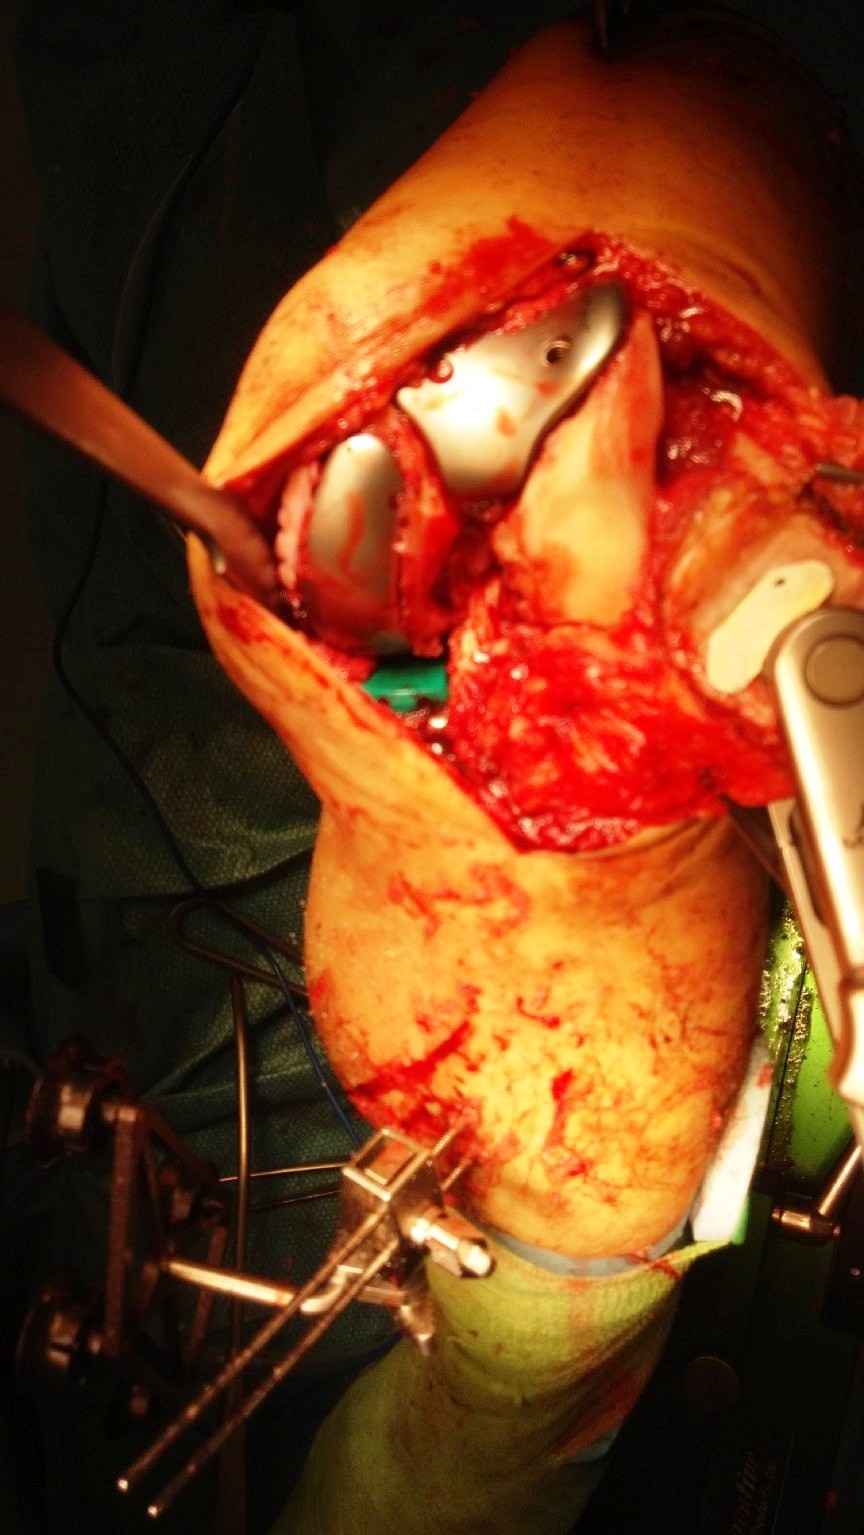

A standand midline incision and medial parapatellar approach was used. The osteoarthritis was confirmed to be mainly affecting the medial and patellofemoral compartments of his left knee.

Registration of the knee were done and the Makoplasty RIO robotic arm was prepared.

Burring of the bone were completed using the RIO robotic arm.

Trial implants showed good positioning of the implants.